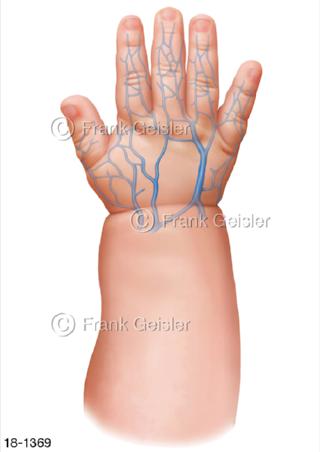

18-1369 Notfall, Venen Baby Kinderhand Kleinkind